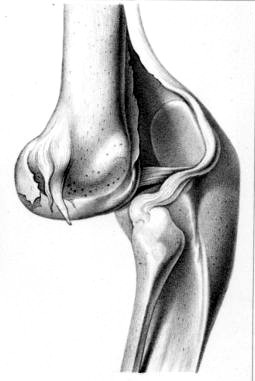

Knee Dislocated Backward, From Ouvrage:

Traite

des fractures et des luxations,

By Joseph

Francois Malgaigne (1855)

The backwards dislocation of a knee is a little more challenging. Atkins says "you are to have an Assistant for the Contra-Extension [pulling the part above the dislocation away from it] above the Knee, and yourself with one Hand on the Calf, and the other above the Ancle, are to extend forwards the Buttock, and it will knap in"4. Wiseman advises that the extension be made by bending the dislocated lower leg "suddenly backward, bringing his Heel to his Buttock"5, which is the same basic procedure as Atkins, albeit a bit more violent. Paré follows suit, although he says the patient should be seated on a bench first with the surgeon positioned behind him to bend the knee all the way back.

Of course, with the exception of the three simple devices used to hold the leg steady and protect it, this is the same procedure as discussed by Atkins and Wiseman. No one shows an image of this form of relocation, although from the image of the backward dislocation, it is easy to see how pulling the lower leg suddenly back and up toward the buttock cause the bone to 'knap in'.